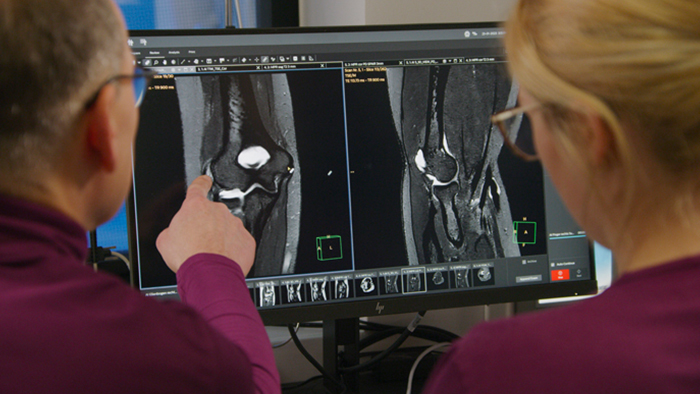

“The big 27-inch 4K high resolution screen makes a total difference. It shows the large planning images with much higher resolution than we were used to. Anatomic landmarks can be more easily identified, which advances the process. Now it is much easier and faster to plan the new sequences and it’s easier for us to find lesions,” says Dr. Schröter.

Another important part of MR Workspace is the graphics processing unit (GPU), which allows on-the-fly reconstruction times for images acquired with SmartSpeed. “In addition to seeing razor-sharp images on the large 4K monitor, we also have better and faster reconstruction of the images. Using this extremely high resolution, we sometimes have sequences with up to 800 individual images. The GPU then manages to convert them in a matter of seconds into multiplanar reconstructions. Very impressive.”